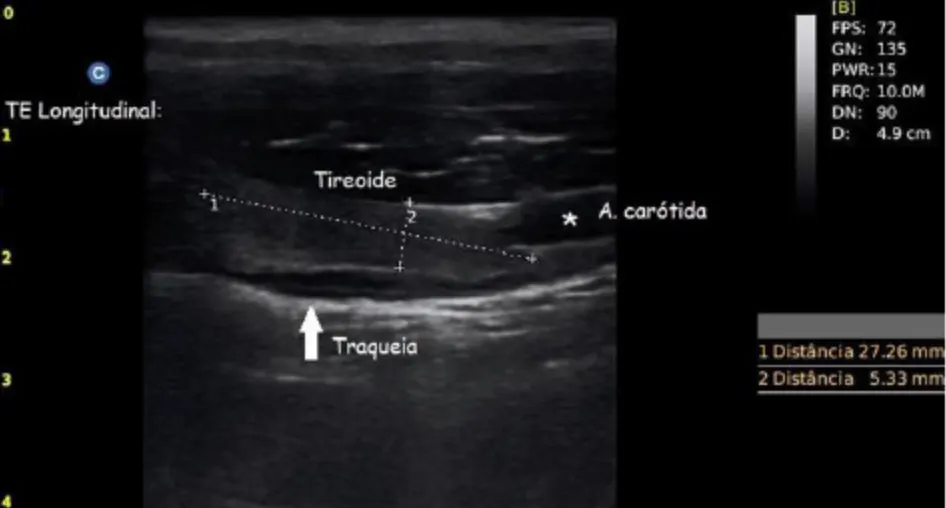

Nieinwazyjne USG szyi powinno stać się rutynowym elementem profilaktyki geriatrycznej — obok badań krwi czy wizyt szczepiennych.

USG pozwala wykryć:

- guzki tarczycy,

- przerosty gruczołu,

- ektopową tkankę tarczycową,

- zmiany niewyczuwalne palpacyjnie.